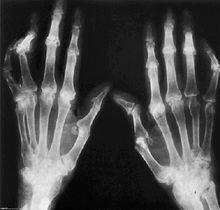

類風濕關節炎:ACR/EULAR2010類風濕關節炎分類標準的問世,為RA的診斷、治療掀開了新的篇章。新標準採用積分形式對疾病進行診斷,要求確定是否具有關節炎證據,並增加了ACPA檢測。廢除了原標準中晨僵、皮下結節、對稱性關節炎及X線平片等項。較之1987年標準,新標準更加注重RA的早期診斷。類風濕因子(RF)、抗環瓜氨酸肽(CCP)抗體等是診斷RA必需的血液學檢查。

是風濕免疫病的主要症狀,也是導致功能障礙的重要原因。風濕免疫病的疼痛中,起源於關節及其附屬結構的疼痛最為常見,然而肢體和軀幹部位的疼痛也可見於內臟和神經系統病變。關節痛、頸肩痛、腰背痛、足跟痛往往是風濕病的主要表現,有時還伴有關節的腫脹。類風濕性關節炎常有對稱性的關節腫痛,手指關節、腕關節尤為明顯;強直性脊柱炎有腰背痛,休息時加重,可伴有足跟痛、紅眼;風濕性多肌痛有頸肩痛、肢帶肌的疼痛及肌無力。關節疼痛,腫,查了血沉很高,類風關因子陽性是風濕病的表現。風濕免疫病常常會引起焦慮症。